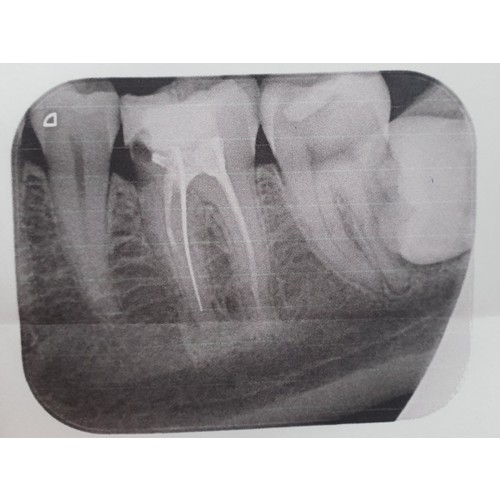

Toevallig hebben ze bij mij vorige week nog een kies getrokken. Ik heb het er toen met de tandarts over gehad en hij gaf aan dat een grote foto inderdaad niet mag, maar een plaatselijke foto geen probleem was. Alleen kunnen ze dan de wortel niet zien. Ze moeten deze foto's soms wel maken uit voorzorg. De verdoving was al helemaal geen enkel probleem, ze verdoven namelijk maar een relatief klein/plaatselijk deel en in mijn geval hebben ze ook iets minder gebruikt, zodat het wel goed verdoofd was, maar niet te lang aanhield.